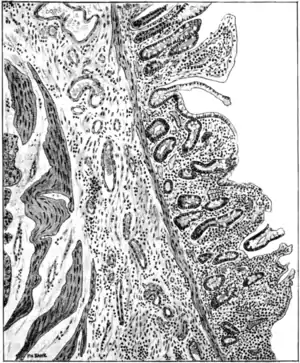

cells and branching mycelium (Bahr), which conceals patches of congestion, of erosion, or even of ulceration, besides such evidences of similar antecedent disease as pigmented areas and thin-scarred, cicatricial patches. The villi and glands are eroded and in many places completely destroyed. Here and there minute spherical indurations, about the size of a pin's head and surrounded by a dark pigmented or congested areola, can be felt in the mucous membrane. On cutting into these, they are found to be minute cystlike dilatations of the follicles filled with a gummy, muco-purulent material. Sections of the diseased bowel (Fig. 83) show under the microscope corresponding changes, such as varying degrees of erosion or ulceration of the surface of the mucous membrane; degeneration of villi, glands, and; follicles; the small mucous cysts referred to; sometimes small abscesses; and, also, infiltration by leucocytes of the basement membrane and submucous layer; and, in the latter, fibro-cirrhotic changes. The mesenteric glands are generally large and pigmented, perhaps fibrotic. The erosion lesions are usually most marked towards the end of the ileum and in the colon; but they may be present in greater or lesser degree universally, or in patches throughout the entire alimentary tract from mouth to anus.

Lesions of the alimentary tract.— The principal and characteristic lesions are found in the alimentary tract. The bowel is thinned to such an extent as to be almost diaphanous. The serous coat is generally healthy, the muscular coat atrophied. The submucosa in places has undergone hypertrophic fibrous changes; and the mucous membrane from mouth to anus, either in patches or universally, is superficially eroded and interstitially atrophied. The internal surface of the bowel is coated with a thick layer of dirty grey, tenacious mucus containing numerous yeast

Morbid anatomy.— Post mortem the tissues in sprue are abnormally dry; fat is almost completely absent; the muscles and the thoracic and abdominal viscera are anæmic and wasted. With these exceptions and certain important changes in the alimentary tract, so far as known there are no special lesions which are invariably associated with this disease. According to Bertrand and Fontan, occasionally certain changes are present in the pancreas— namely, fatty or granular degeneration of the cells, with softening of isolated acini and slight inflammatory infiltration of the connective tissue. These, however, are not more constant than are certain other and similar changes occasionally found in the liver and kidneys. Sections of the tongue show desquamation of the epithelium, especially from the surface of the fungiform papillæ; an invasion of the epithelial cells by yeast fungi has been shown by Kohlbrügge to take place and is possibly a terminal infection.